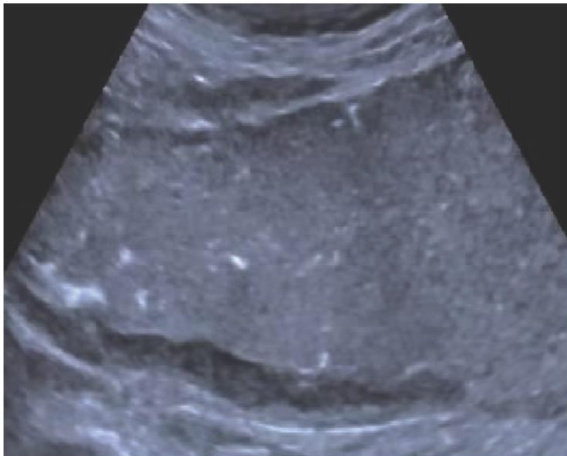

巨大肥厚性胃炎(Menétrier’s,MD)是一种罕见的特殊类型肥厚性胃炎,发病率低于1/20万[1],其病因尚未完全明确,在中年男性群体中更为常见。(剩余8733字)